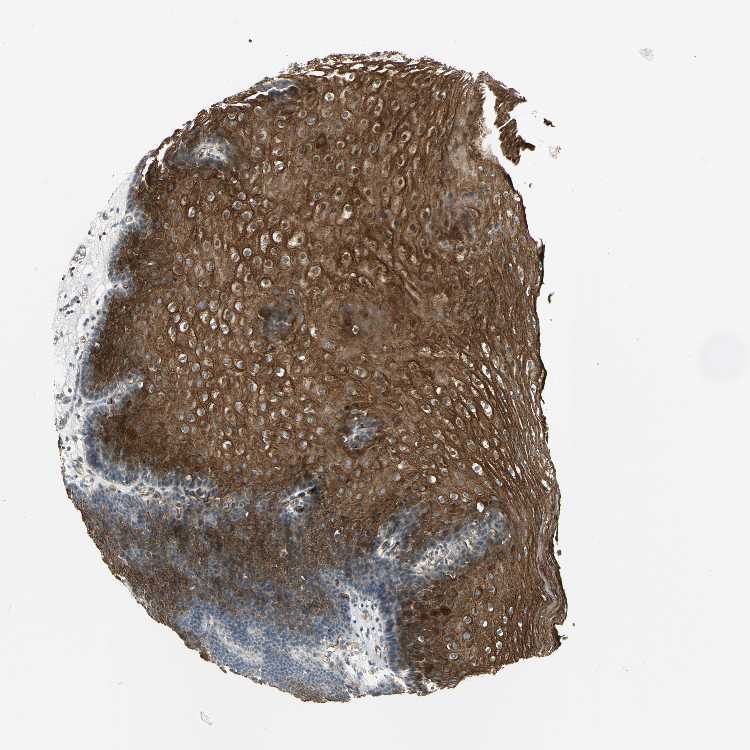

ESOPHAGUS - Antibody stainingi

Antibody staining in the annotated cell types in the current human tissue is reported as not detected, low, medium, or high, based on conventional immunohistochemistry profiling in selected tissues. This score is based on the combination of the staining intensity and fraction of stained cells.

Each image is clickable and will lead to virtual microscopy that enables deeper exploration of all samples and also displays staining intensity scores, fraction scores and subcellular localization as well as patient and tissue information for each sample.

Antibody HPA005928

Squamous epithelial cells High